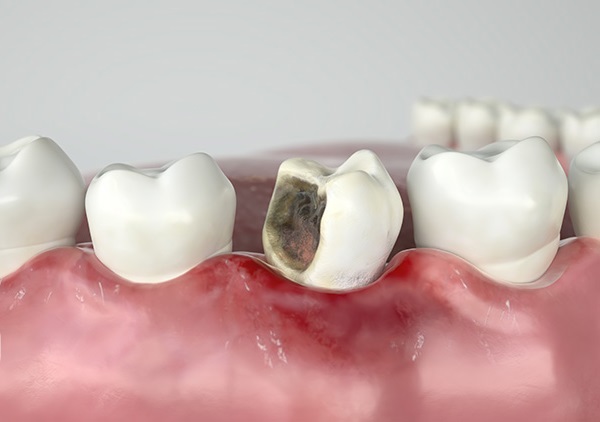

+ Do bệnh lý

Cũng do men răng yếu hơn so với bình thường mà người già là đối tượng thứ 2 (sau trẻ nhỏ) rất dễ mắc các bệnh răng miệng, phổ biến nhất là sâu răng, viêm nướu và viêm nha chu. Nếu không điều trị kịp thời, những bệnh lý này đều dễ dàng “cướp” đi vài chiếc răng trên khuôn hàm chỉ trong một thời gian ngắn.